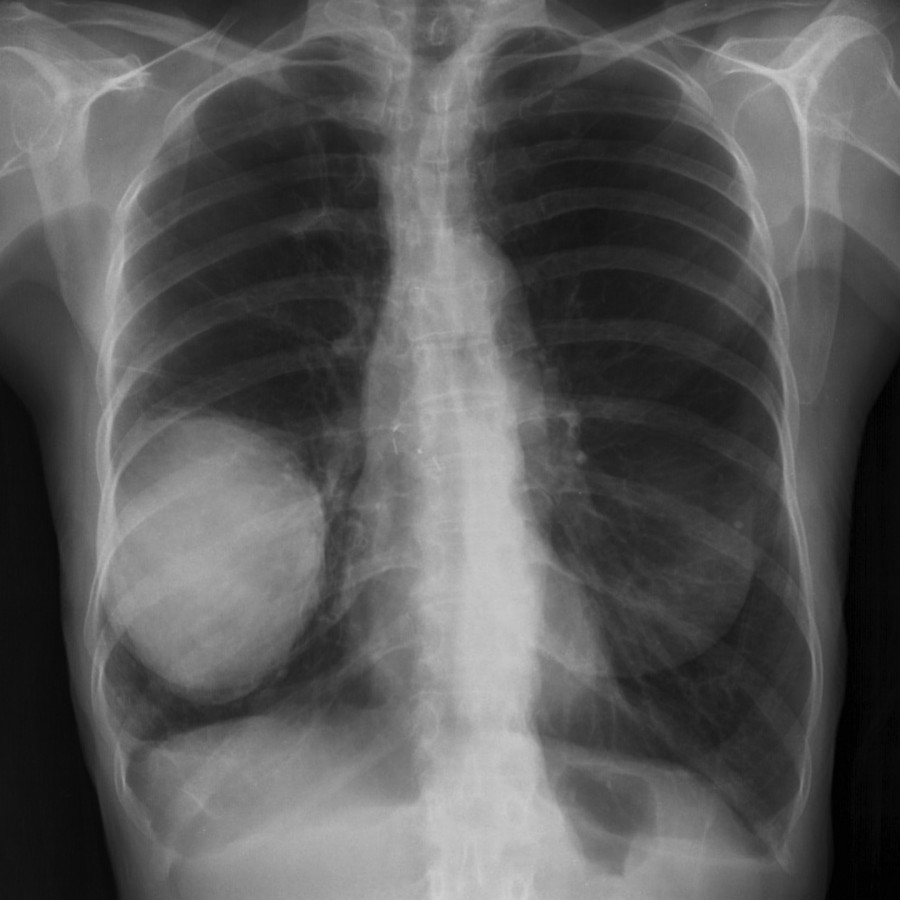

In Fase attiva si ha l'ulcerazione della mucosa dei #Bronchi con il preciso intento di allargare il lume bronchiale e permettere il miglior passaggio di aria.

Nella fase PCL si ha la riparazione delle ulcerazioni e la comparsa di tessuto supplementare e iperplastico, erroneamente considerato patologico, vi è ulcerazione, in Fase di riparazione le ulcere si chiudono. Talora le recidive conflittuali e le conseguenti riparazioni possono causare la crescita abnorme di tessuto che può ostruire il bronco e creare l'Atelettasia.

# L'AdenoCa polmonare coinvolge gli Alveoli polmonari. Il conflitto che sta' alla base di questa manifestazione è il conflitto ancestrale di Paura di morire, di non poter più respirare. Condizioni di stress elevato specialmente inFamiglia ed al lavoro, possono precipitare la situazione quando intervenga un episodio scatenante.

In fase attiva si ha proliferazione tissutale in funzione di aumentare la superficie di scambio gassoso. A problema risolto si ha lo smantellamento di questo tessuto ad opera principalmente dei Micobatteri, con la formazione di focolai o caverne tubercolari.